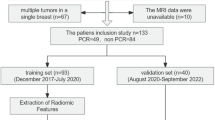

In this retrospective study, we initially recruited 657 patients, from two institutions, with nonmetastasis invasive breast cancer who received NAC as planned before surgery. The inclusion criteria were (1) patients pathologically diagnosed with primary invasive breast cancer; (2) radical surgery performed after completion of NAC; and (3) breast MR examination conducted within 2 weeks before NAC. Radical surgery refers to the resection of primary tumor lesion with negative margin. The specific surgical methods include segmental mastectomy breast-conserving surgery, nipple-sparing mastectomy, simple mastectomy, modified radical mastectomy, and radical mastectomy for breast cancer. The exclusion criteria were (1) patients with nonductal breast cancer; (2) MRI images insufficient to assess efficacy; (3) treatment other than NAC had been performed before the operation; and (4) patients with unavailable postoperative pathologic results or pCR was not assessed. Of these, 448 patients met the criteria for the final analysis.

A total of 448 patients with primary invasive ductal breast cancer were finally enrolled (Fig. 1). The median age was 46 years (IQR 39–53) and the median tumor size was 3.6 cm (range 0.6–12.0 cm). Among all patients, 55 (12.1%) patients reached pCR, while 399 (87.9%) were placed in the non-pCR group. The pCR rate in the training and validation cohorts was 10.5% and 18.5%, respectively. Patients with estrogen receptor- and/or progesterone receptor-positive and HER2-negative status were placed in the hormone receptor (HR)-positive subgroup, accounting for 52.2% of patients; patients with HER2-positive status were placed in the HER2-positive subgroup, accounting for 39.7% of patients; and patients with HR-negative and HER2-negative status were placed in the triple-negative subgroup, accounting for 8.1% of patients. For TNM stage, 56% patients had stage I–II disease and 44% had stage III disease. Demographic and clinical baselines of the training and validation cohorts are summarized in Table 1.